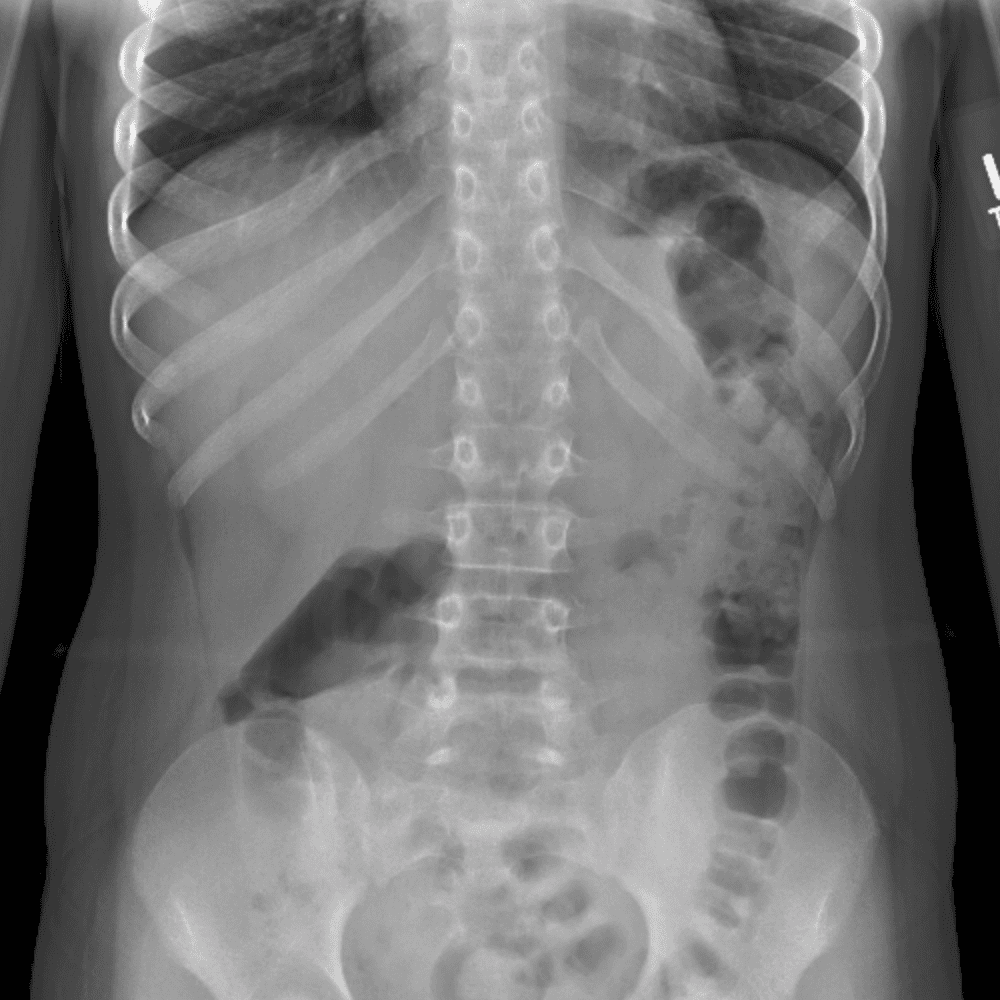

Peds Abdomen

Practice

Simulates call by including subtle or difficult cases and some normals.

30 cases